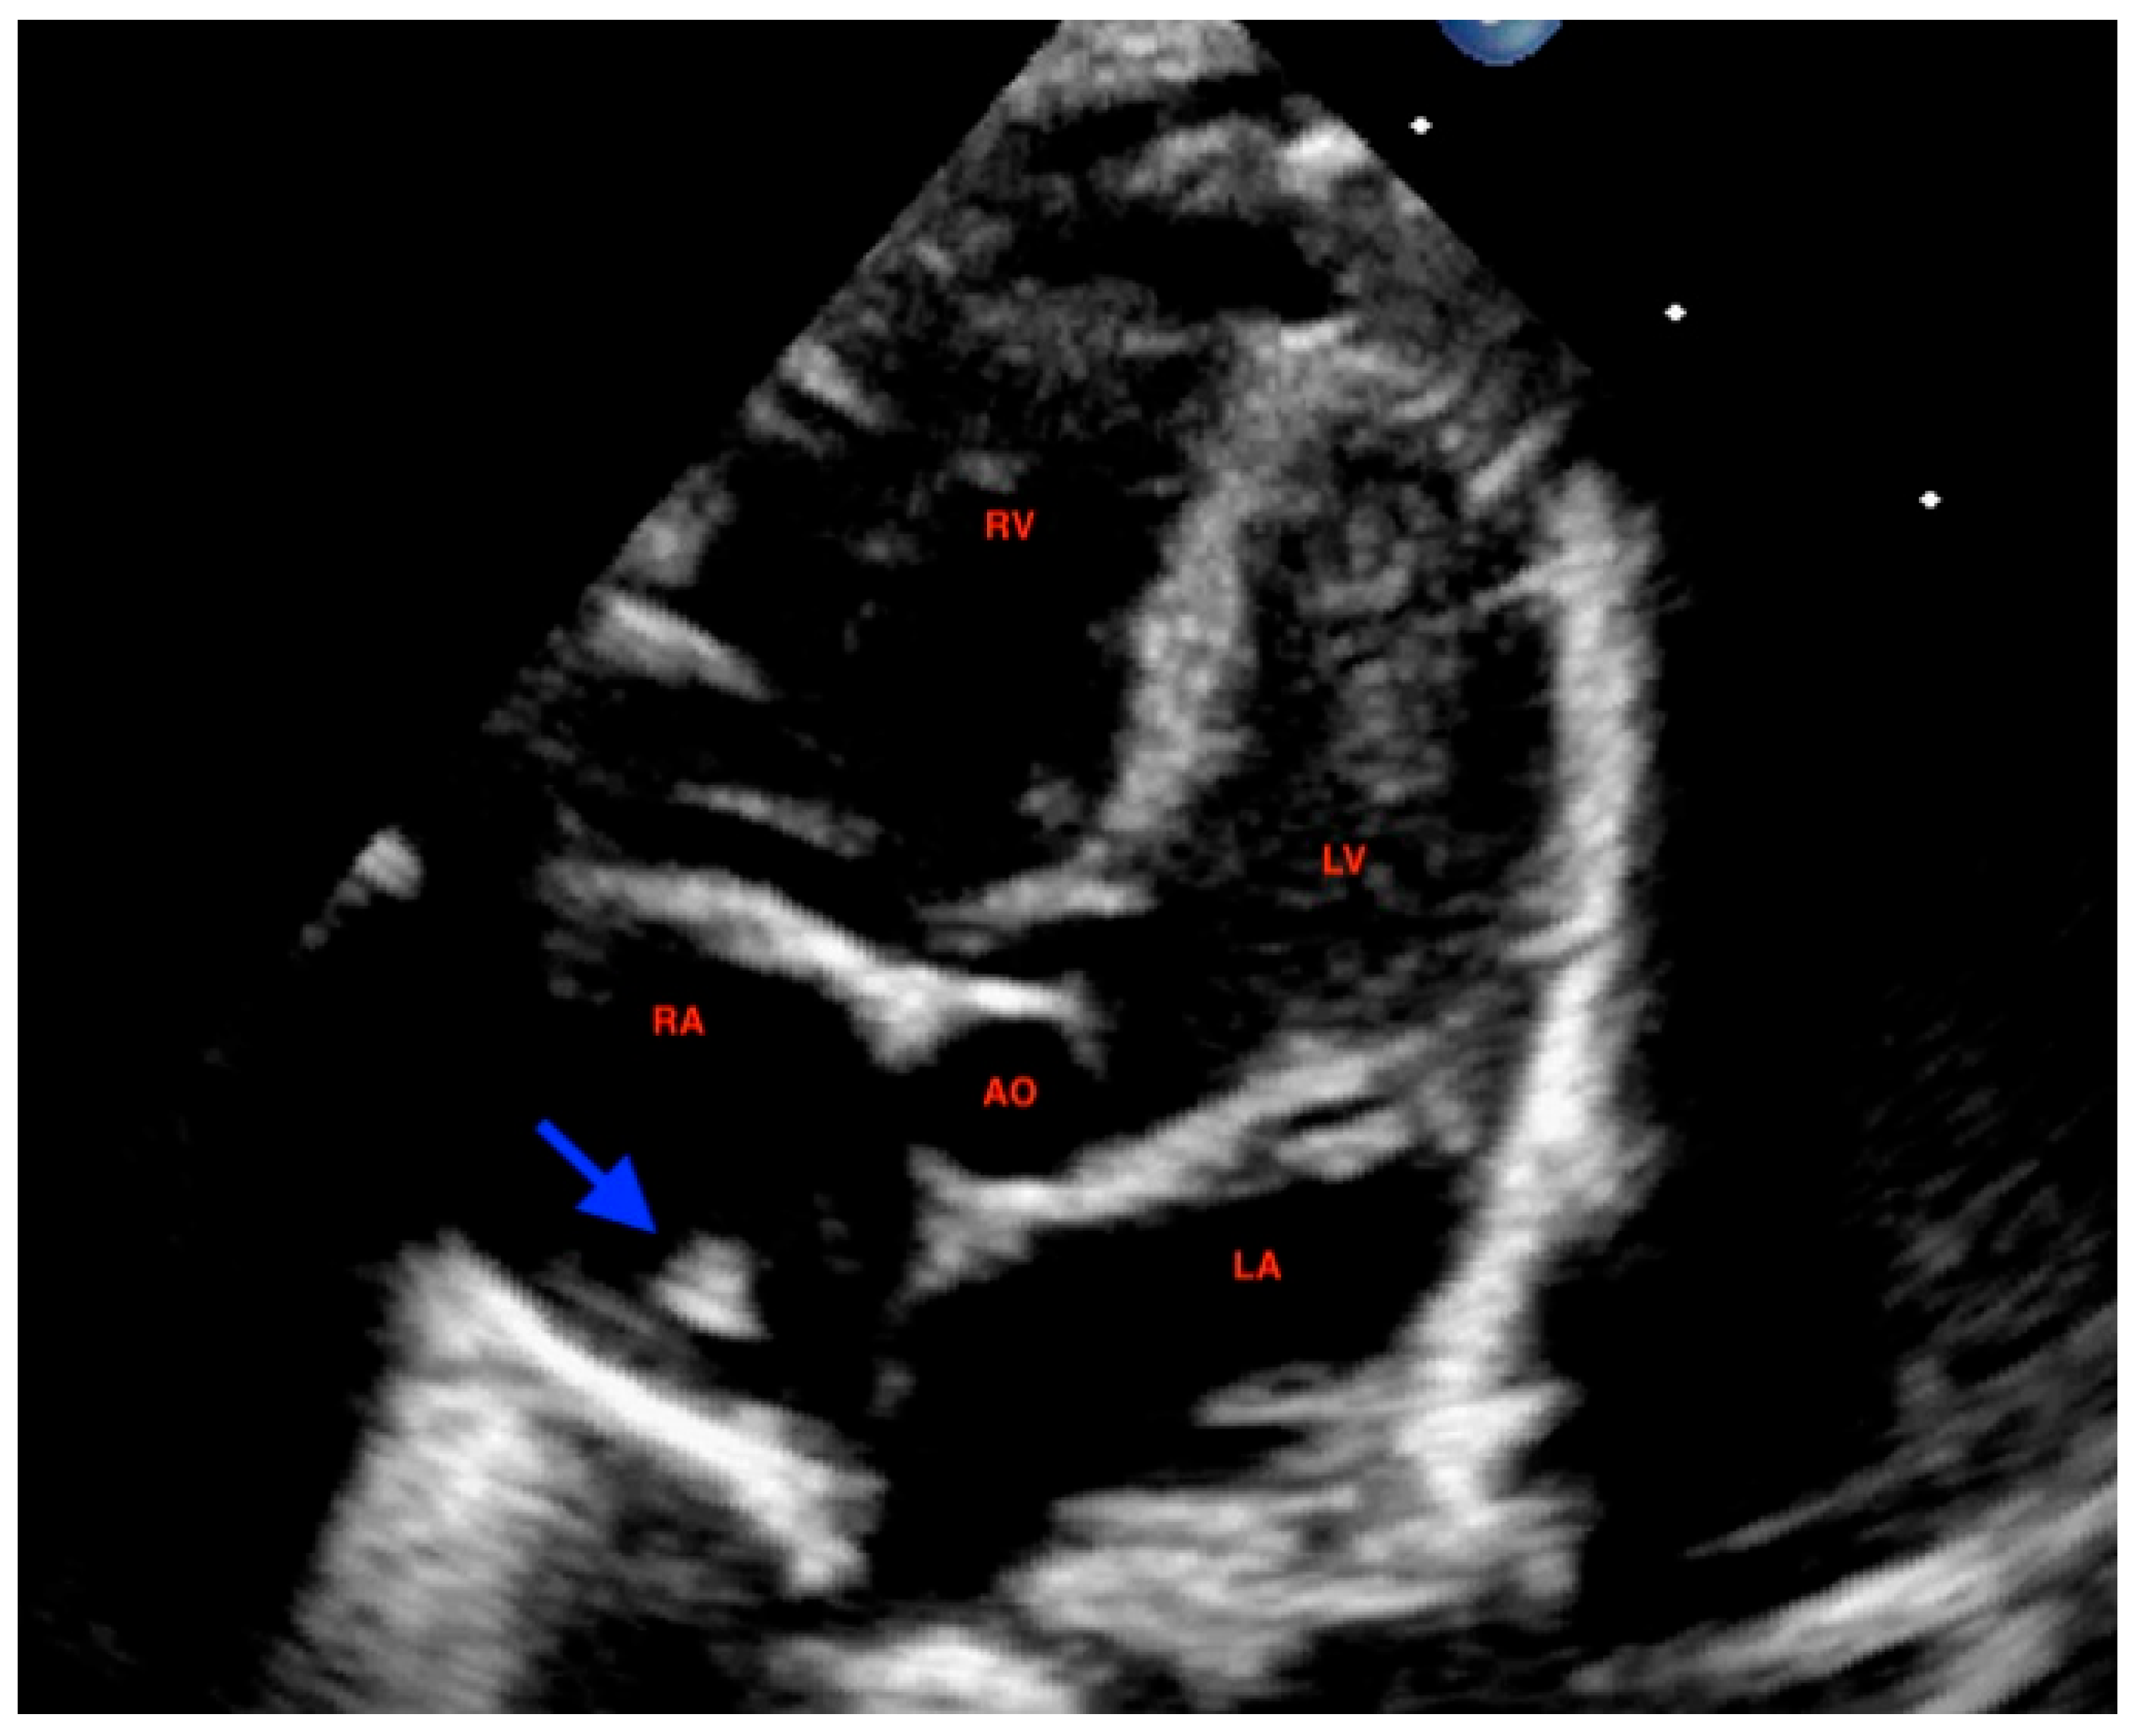

At 72 h of life, postnatal transthoracic echocardiography demonstrated a persistent hyperechoic mass in the right atrium, not grown and not modified compared to previous scans, and interpreted as HCT. There was no evidence of right atrial inflow obstruction, and no mass growth was observed (Figure 3).

Figure 3. Postanatal apical 5-chamber view: echocardiography at 72 h of age displayed a persistent hyperechoic mass (arrow) within the right atrium compatible with hypertrophic crista terminalis. The structure showed no variations in growth compared to previous scans. RA: right atrium; RV: right ventricle; LA: left atrium; LV: left ventricle; AO: ascending aorta.